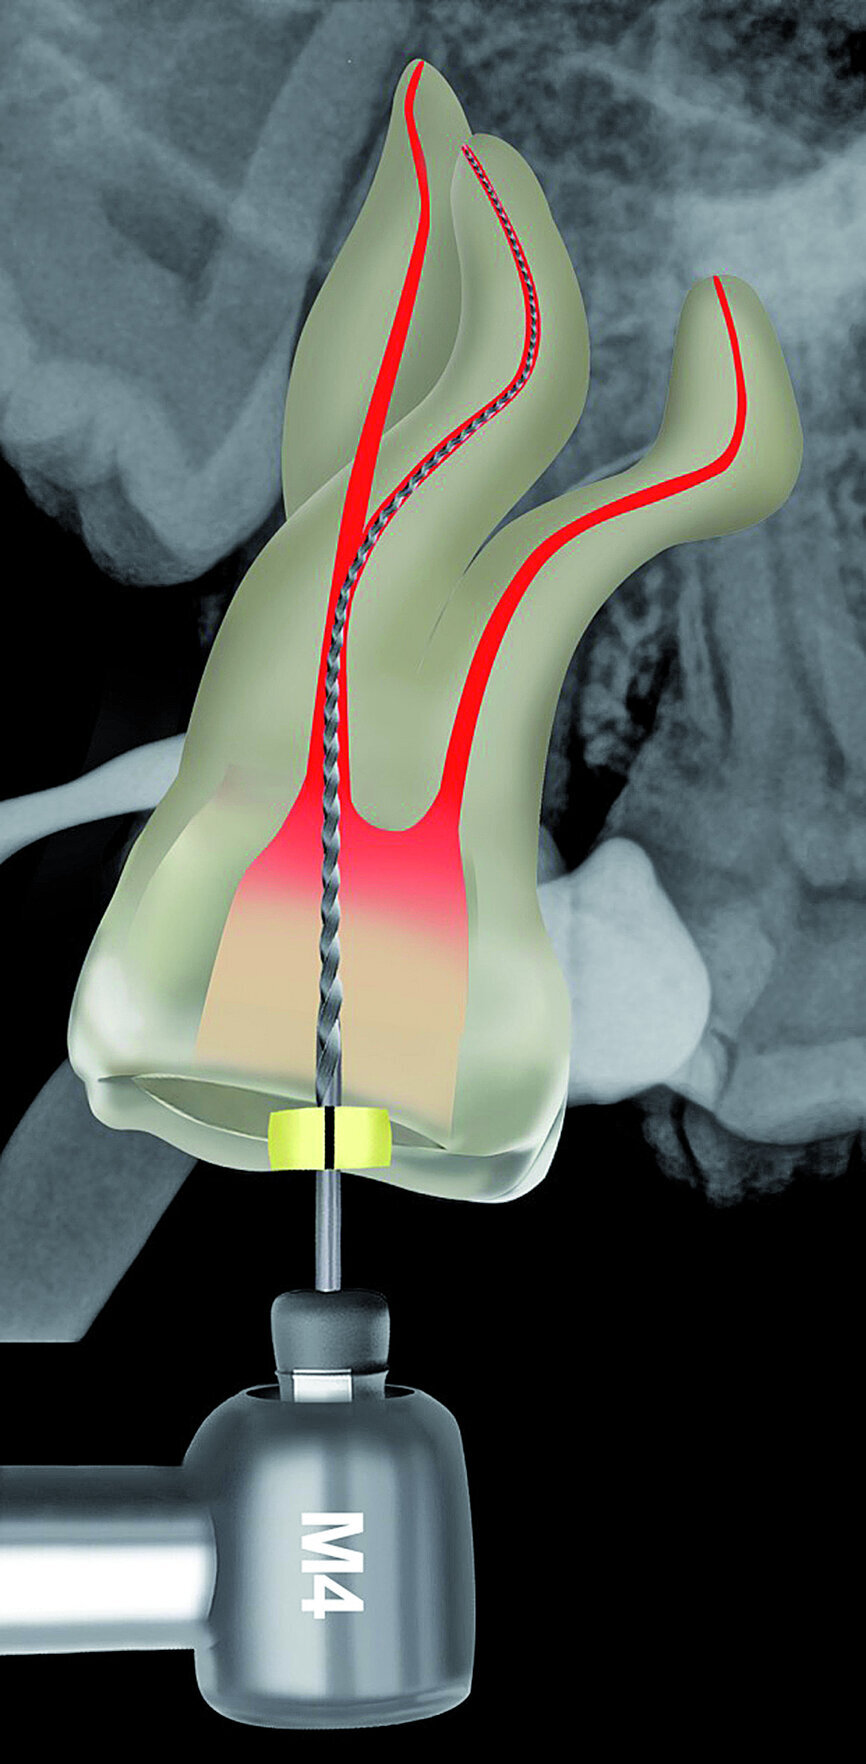

Fig. 22: After the Size 08 K-File, a size 10 K-File was made ‘super loose’ to complete the preparation of the reproducible micro glide path.

The pulp chamber was filled with Glyde (Dentsply Sirona) before the canals were carefully negotiated to full working using pre-curved size 08 K-Files (Fig. 19). Working length measurements obtained from an electronic apex locator reading corresponded with the lengths obtained from the 3D Endo Software. These measurements were also confirmed radiographically (Fig. 20). A reproducible glide path was prepared in each root canal system with the size 08 K-File in an M4 Reciprocating handpiece (Sybron Endo; Fig. 21), followed by making a size 10 K-File ‘super loose’ (Fig. 22). A ProGlider (Dentsply Sirona) was used in a rotary motion to expand the glide path in the palatal root canal (Fig. 23). Considering the sharp and severe curvatures in the two buccal canals, it was decided to convert the ProGlider instrument into a manual file to expand the glide path in these tortuous canals with more safety (Fig. 24). The manually adapted ProGlider was used in a balanced force motion up to working length. In addition, to create more safety during the canal preparation of the two challenging buccal root canals, it was also decided to use the reciprocating WaveOne Gold Glider (Dentsply Sirona; Fig. 25), after the ProGlider instrument to further expand the glide paths. The WaveOne Gold Glider was used in 4–8 backstroke brushing motions from working length, in the two buccal root canal systems.

In 2006, West recommended using K-Files with an initial watch winding motion to remove restricted dentine in very narrow canals, followed by a vertical in and out motion with a 1 mm amplitude and gradually increasing the amplitude as the dentine wall wears away and the file advances apically. [11] Several authors have described the use of a small K-Files driven by a reciprocating handpiece for initial glide path preparation, especially in very constricted or curved canals. [12, 13] The main advantages of using the reciprocating M4 handpiece is to reduce the glide path preparation time, hand fatigue, and to secure the canal in narrow, multi-planar root canals faster compared to the conventional manual technique. [14] Securing the two multi-planar buccal root canal systems in this case, with a size 08 K-File in the M4 reciprocating handpiece, facilitated further glide path enlargement.